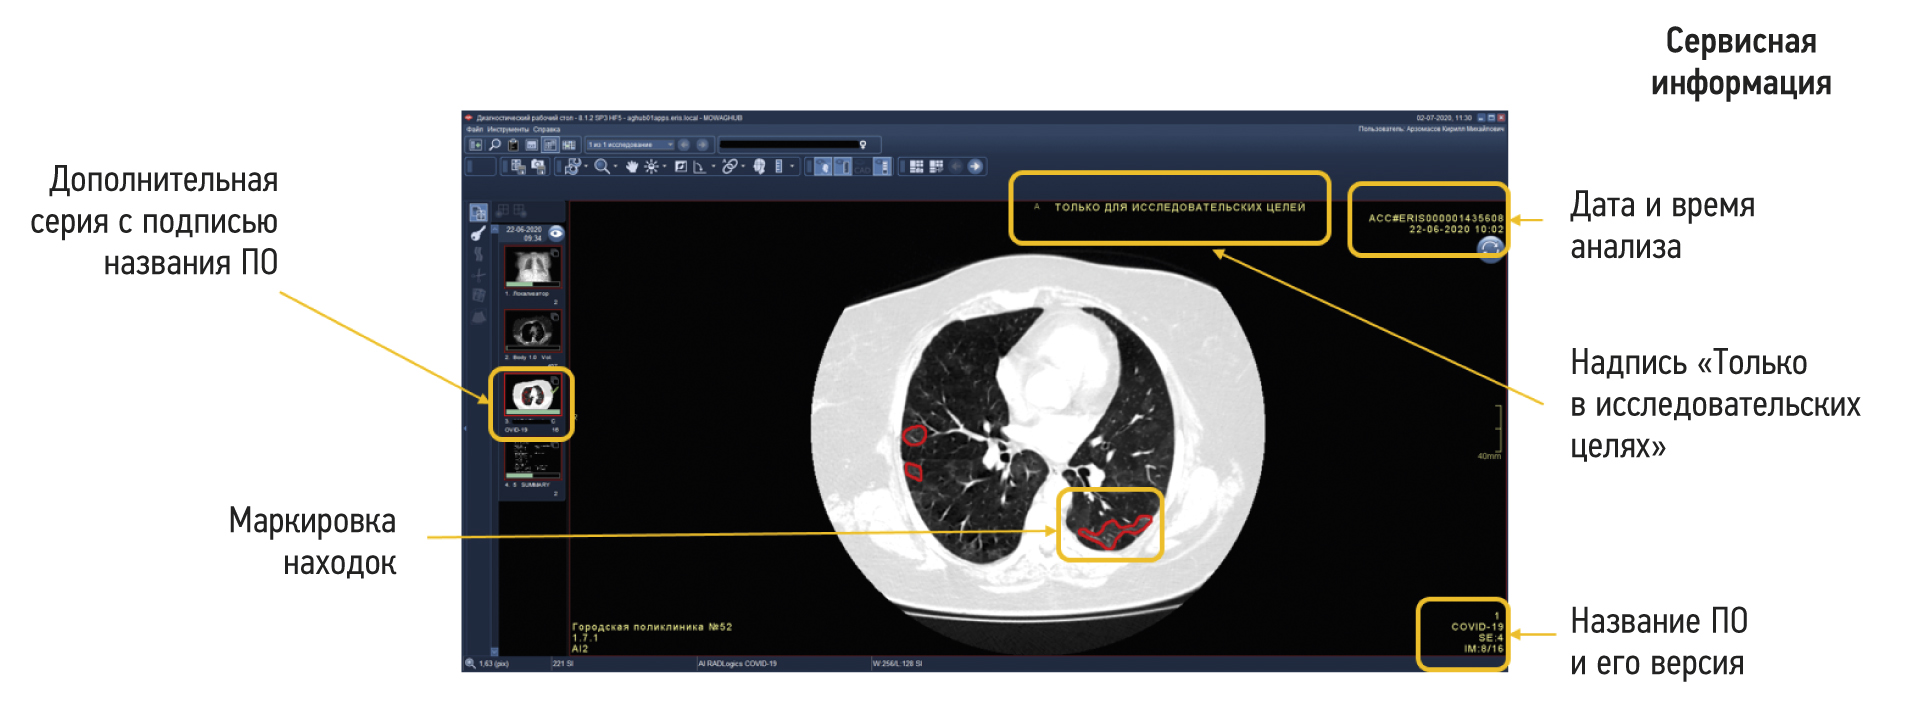

Functional testing is a stage wherein software functions specified by a supplier are checked for availability and functionality. This testing is performed at the technical and clinical levels. On a technical level, the software is assessed based on the following criteria: prioritization of research (triage), availability of an additional series of images from the software, presence of the other series’ name, presence of a graphical designation of software on the images of the different series, presence of a warning label “For research purposes only” on images and in DICOM SR, possibility of series synchronization, displaying the probability of abnormality, indication of the category of abnormality, and availability of complete DICOM SR protocol structure (Figures 2 and 3).

Fig. 2. Main components of the result of using artificial intelligence–based software with images: A reference example.

Fig. 3. Main components of the result of using artificial intelligence–based software with DICOM SR: A reference example.

This part of functional testing should be performed by technical specialists in accordance with the basic functional requirements developed by the Moscow State Budgetary Institution “Scientific and Practical Clinical Center for Diagnostics and Telemedicine Technologies of the Moscow Department of Health” (Center for Diagnostics and Telemedicine).14 The medical assessment of software functions should be performed by medical experts in accordance with basic diagnostic requirements developed by the Center for Diagnostics and Telemedicine.15 Basic diagnostic requirements include criteria, such as mandatory and optional content of software response, format, and form of the submitted response. Basic functional and diagnostic requirements contain common requirements for all software and specific requirements based on the clinical task for which the software is designed.

If critical nonconformities are identified, software testing is stopped until the supplier eliminates their causes. Inconsistencies with basic functional requirements are critical because they negatively affect the HCP work processes and, directly or indirectly, the patient’s life and health (Figures 4 and 5).